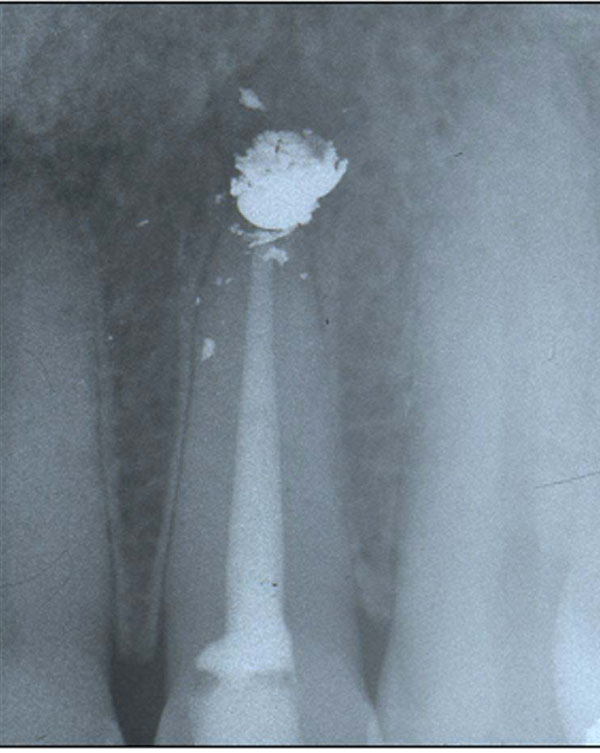

Two months later the first dentist performed a second surgical revision of the apex by means of an intrasulcular incision creating a flap by using Velvart’s technique [20], osteotomy by ultrasonies, removal of the obturation material confirming the presence of amalgam and its scattered fragments in the bony cript. The prior resection of the apex was confirmed by the presence of a chamfer which was eliminated and followed by the preparation of the cavity using ultrasound to a depth of 3mm. The obturation material chosen was MTA (Fig. 7).

Case 2. Radiological exam after the second apicoectomy and retrograde obturation with MTA of 1.2 (first dentist).